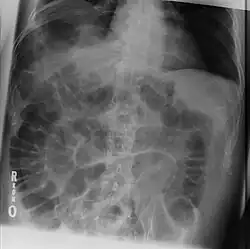

- Rigler's sign